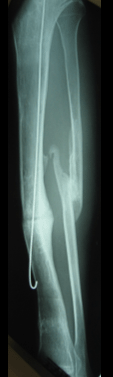

Post

Op

SURGICAL TREATMENT

▪ 28/4/1999

▪ Sequestrectomy (5 cm bone block removed)

▪ Gentamicin beats

▪ Trifocal Ilizarov bone transport and compression

▪ 5 Ilizarov ring configuration

▪ IM tibia guide wire inserted

2 weeks

1 month

Progress

▪ Tibia united S/E

▪ Good return of knee and

ankle function

▪ Limb alignment and

shortening restored

8 months

Patient able to full weight bear with no shortening and residual tibia deformity